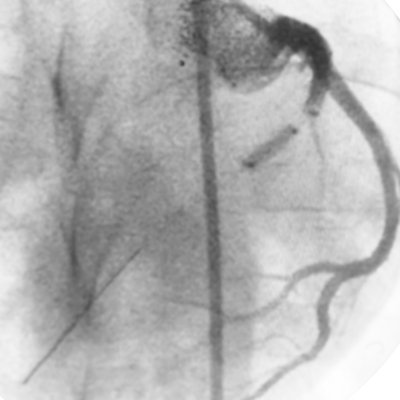

Rumpel Leede phenomenon after ulnar artery access for LHC. Petechial and nontender with distinct margin at hemostasis band. First time I’ve seen it. Benign event that resolved with time but can be alarming to patient and operator if not recognized. #RadialFirst